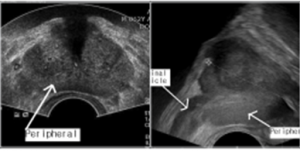

환자는 옆으로 누운 자세로 검사를 받는데, 검사자는 초음파 탐색자 (probe)에 콘돔덮개 (condom cover)를 씌운 다음 젤리를 충분히 바르고 항문으로 탐색자를 천천히 삽입한다. 이때 항문으로부터 7~10Cm 사이에서 대개 전립선이 관찰되며 가로영상 (axial view)과 시상면 (sagittal view)를 모두 보기 위해서는 초음파기계의 종류에 따라 탐색자를 90도로 회전해야 할 수 있다. TRUS를 통해 전립선의 크기, 전립선 내부형태 (석회침착, 저에코성 병변, 정중낭종), 피막의 연속성 등을 관찰할 수 있는데, 일반적으로 전립선암의 대부분은 말초대 (peripheral zone)에서 발생하므로 말초대의 저에코성 병변 (hypoechoic lesion) 이 있다면 눈여겨 봐야 한다. 이 경우 피막과의 관계도 잘 살펴봐야 한다. 경직장 초음파검사는 전립선암의 진단에 있어서 절대적이지 않음을 명심해야한다. 가끔 방광종물이 발견되기도 하므로 주변조직에 이상이 없는지 살펴봐야 한다. 전립선 초음파를 시행한 후 반드시 직장손가락검사(DRE)를 시행하여 전립선에 대한 촉진 결과를 동시에 기술해야 한다.

좌측 그림은 가로영상이며 화살표는 말초대를 가리킨다.

우측 그림은 시상면을 나타내며 방광의 후벽에 인접하여 정낭 (seminal vesicle)이 관찰된다.